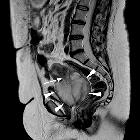

Radiographic features

MRI

In the pelvis may add further to CT in delineated the tumor's relationship to adjacent organs and identifying lymph node disease.